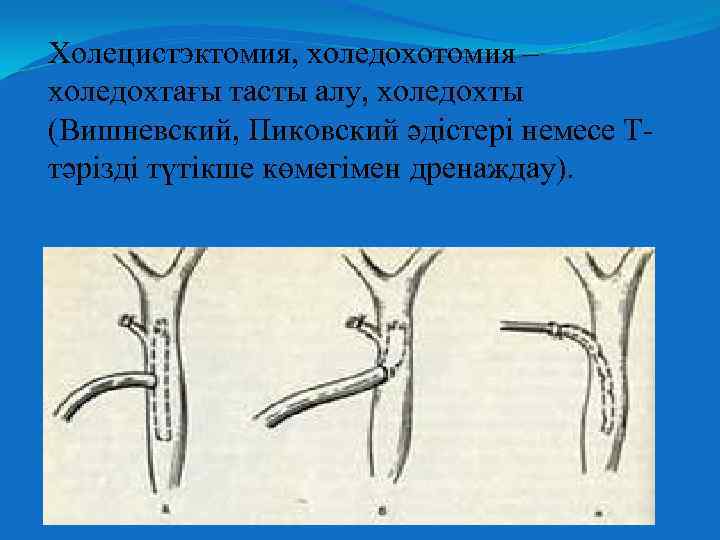

Холецистэктомия, холедохотомия – холедохтағы тасты алу, холедохты (Вишневский, Пиковский әдістері немесе Ттәрізді түтікше көмегімен дренаждау).